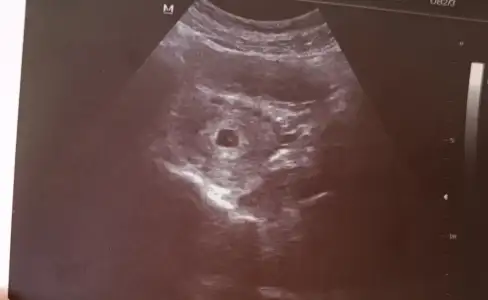

Benim 4+6 da çok çok küçük göründü canım alttan bakıldıMasallah Allah sağlıkla kucağınıza alabilmeyi nasip etsin kac günlükte gorundu kese bende 4+6 da gidicem de doktora acaba kese görünür mu

Ooyyy maşallahÇok şükür benim de kesem düzelmiş doktor hiç korkma çok güzel, yolk kesesi de oluşmuş kalbi de oluşmuştur ama şimdi dinlemeyelim dedi![]()

1 hafta sonra gel bakalım dediAyyy maşallah canım çok sevindim darısı kalp atışına diyelim o zaman insallahhne zamane verdi randevuyu kalp atışı için ?

normalde ben eminim bugün de kalp atışı duyulurdu ama ben eski doktoruma geldim cihazı çok çok eski normalde kalp atışı için bile 9. Haftada çağırıyor düşün yani